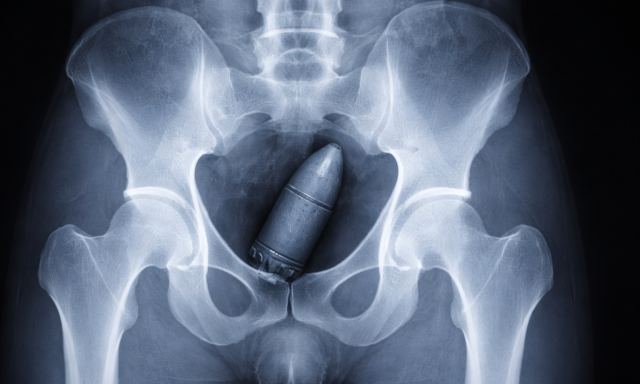

Világháborús bombával a seggében jelentkezett az ügyeleten, az egész kórházat ki kellett üríteni